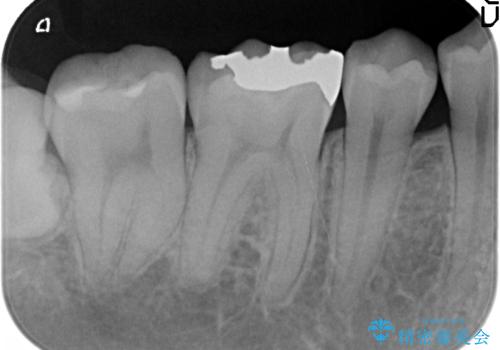

- 右下の銀歯が気になるといらっしゃった方の症例です。

右下6番目の銀歯を除去後、セラミックインレーによる修復を行いました。